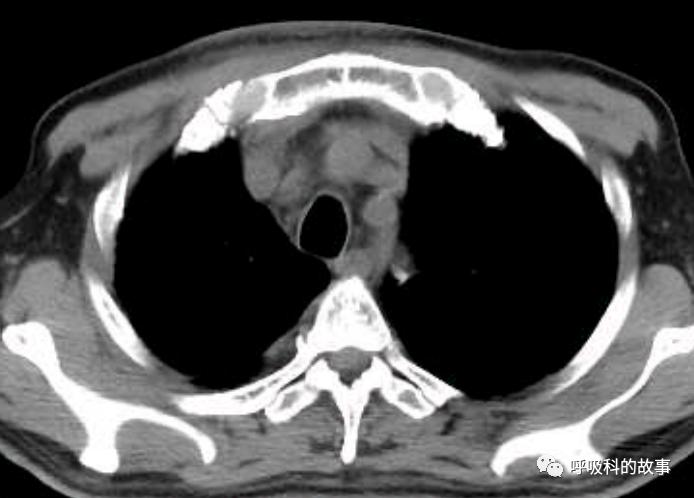

当时我们也曾经考虑给病人做淋巴结活检,但再次遭到患者的拒绝,由于患者体温正常,症状好转,我们也没有坚持。经过了两个多月的伏立康唑治疗,肺部影像基本吸收。

纵隔淋巴结也明显缩小了